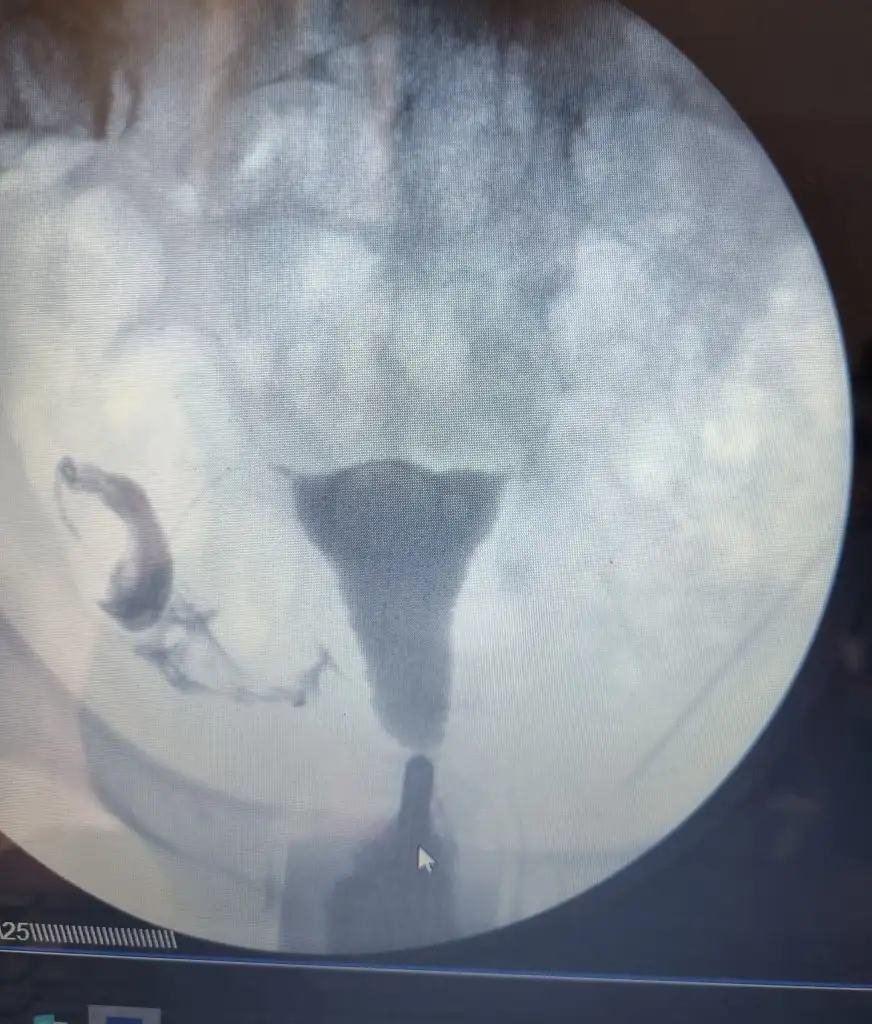

Arkadaşlar sol tüp kapalı çıktı ama sağ tupte sıvı birikmesi var mı sizce? Doktor sorun yok dedi ama sanki sıvı birikmesi örneklerine de benzettim..

Eklentiler

• image.webp

image.webp

45,4 KB · Görüntüleme: 130